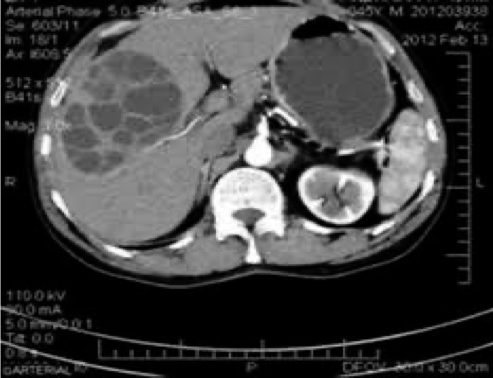

• ultrasound and CT scan can show the site, size and daughter cyst in the liver

Hydatid cyst (multiple daughter cyst) in the right lobe of the liver